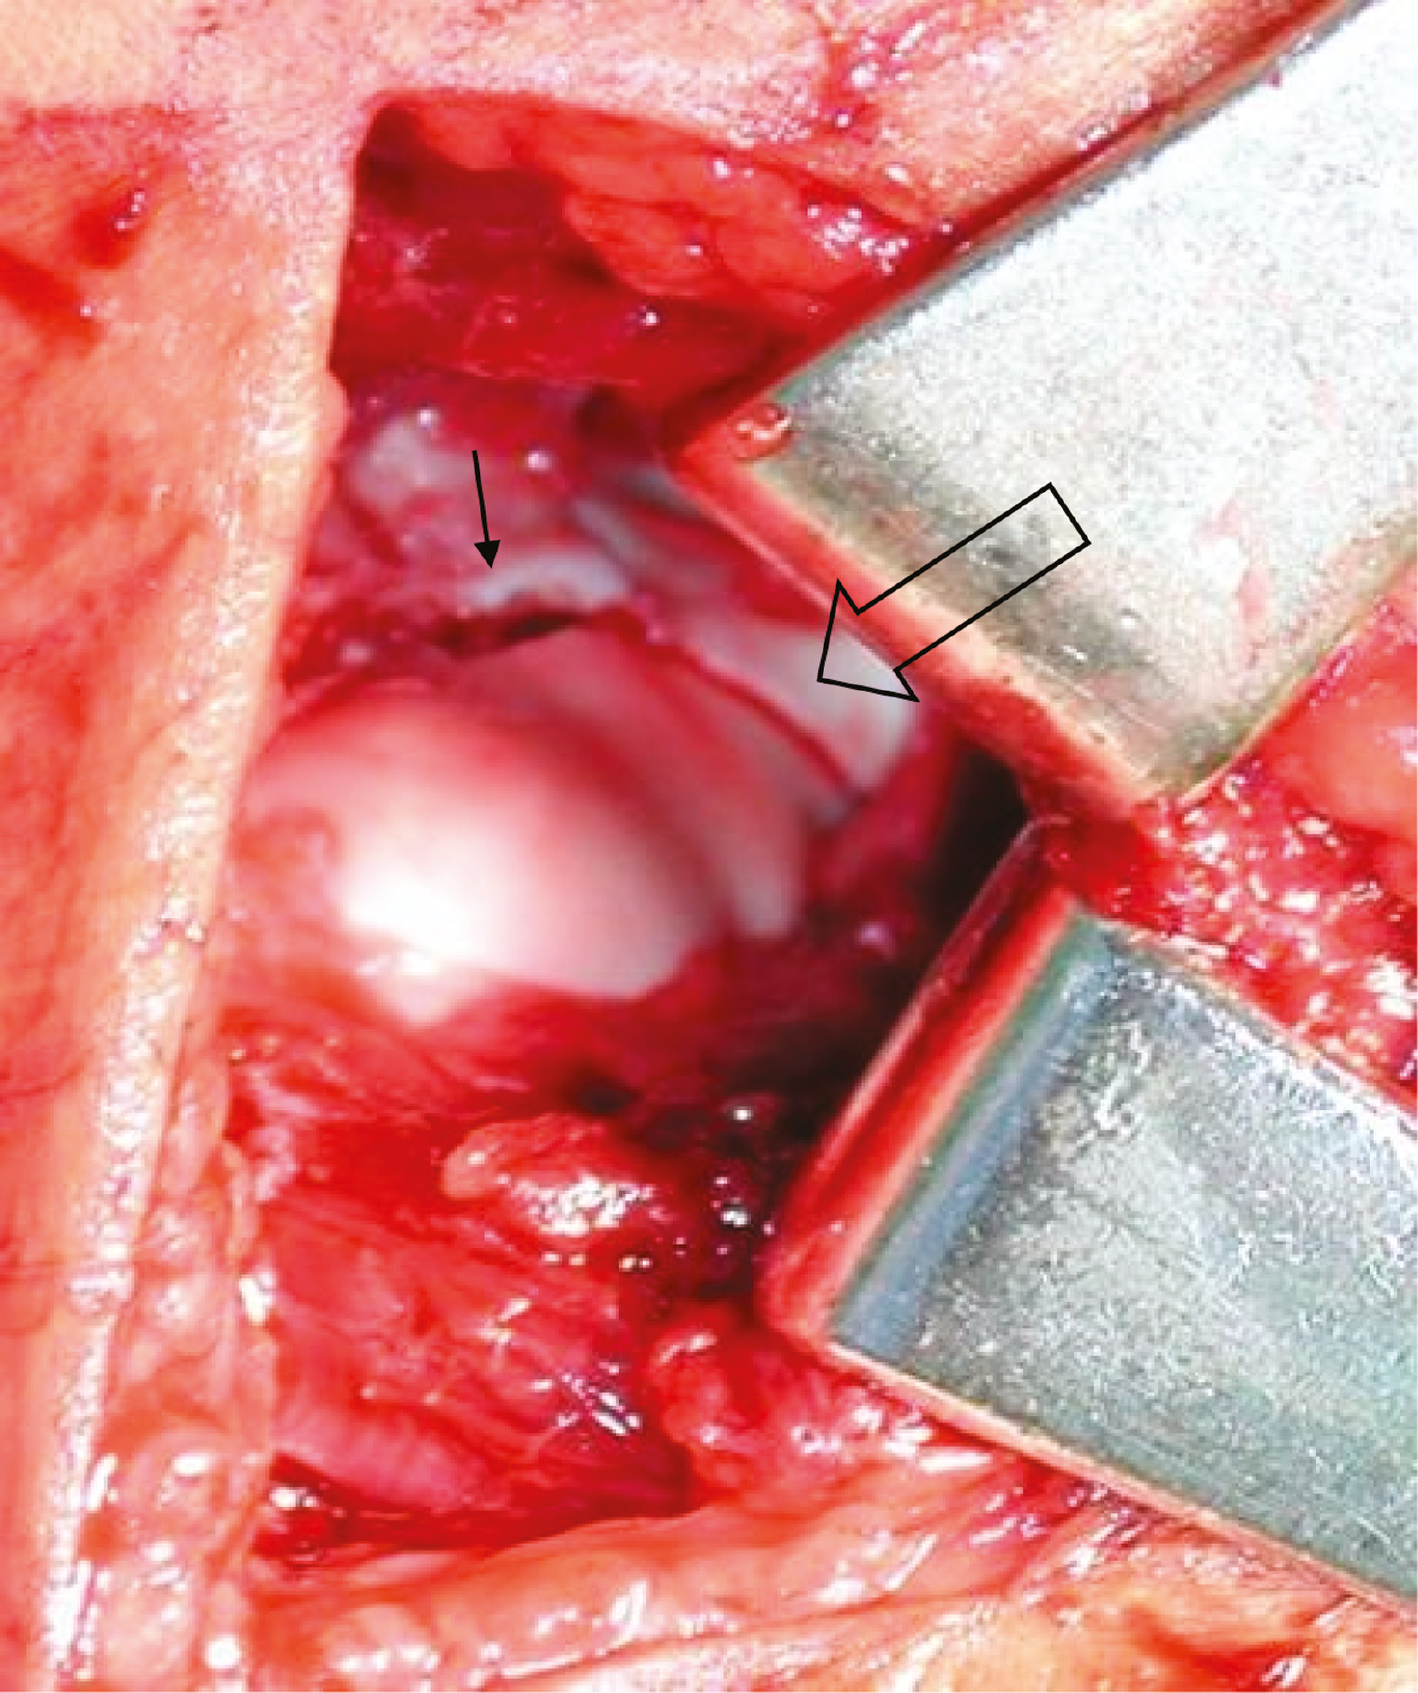

It is key to improve visualization by incising a small portion of the anterior capsule off the distal humeral fragment and extending the dissection distally until the radiocapitellar articulation is visualized. Dissecting off a small portion of the attached antero-lateral muscle from the lateral condyle fragment will complete the visualization needed to properly assess fracture reduction. Posterior dissection should be avoided to minimize risk to the capitellar blood supply (Figure 10).

Figure 10. Intraarticular inspection is facilitated by release of anterior capsule and muscle.

Small Bennet, Army-Navy, or malleable retractors can be placed carefully across the anterior aspect of the distal humerus to allow for inspection of the articular surface. It is important to thoroughly prepare the fracture bed in order for the fracture to reduce anatomically. A lighted suction tip or headlight can be very helpful to visualize the joint surface. A variety of instruments can be utilized for reduction including towel clip, dental pick, sterile fork, or the surgeon’s thumb. Reduction can be facilitated by relaxing the extensor muscles by keeping the wrist extended (Figure 11).

Figure 11. Keeping the wrist extended can help relax the extensor muscles and facilitate reduction.

Success in this technically challenging procedure is best achieved with the use of an assistant—one surgeon holds reduction while another places the pins. Through direct visualization (Figure 15) and then palpation of the articular surface with a Freer elevator, the reduction is verified with fluoroscopic confirmation of reduction and proper pin placement. If there is concern about stability, a third pin can be placed in a divergent fashion. Good results have also been achieved utilizing a single 3.5/4.0 mm partially threaded, cannulated screw if greater stability is indicated. It should be oriented perpendicular to the fracture plane and often a second wire is placed to control rotation during drilling and screw insertion. This screw may become symptomatic in the future and necessitate elective removal.

Figure 15. Direct visualization of the articular surface of the distal humerus after closed reduction and pinning of the lateral condyle fracture. Notice the anatomic reduction of the articular surface (open arrow) with associated small amount of metaphyseal gapping superior to the articular surface (small arrow). Photo courtesy of Gregory Mencio, MD.